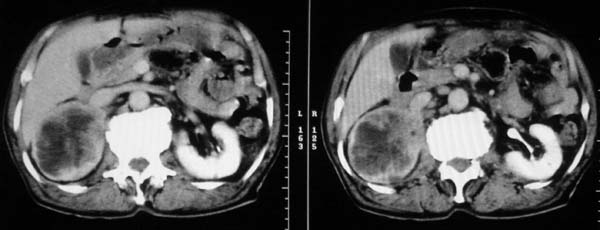

男性,80岁,腰痛数月,因“前列腺增生”申请b超检查,发现“右肾占位”,遂行ct检查。

右肾正常结构消失,且肾功能差(延时显影),个人认为需考虑结核或其它感染性病变。肿瘤不是很像。

病变范围广,肾影增大,病变累及肾实质及集合系统,皮质变薄,病灶内见不规则坏死液化灶,同时累及邻近的肝实质及周大肌,考虑:感染性病变(结核或炎症)可能性大

右肾区巨大混杂密度影,不均匀强化,与腰大肌分界不清,首先考虑:肾癌可能性大,鉴别:肾结核(肾实质内常多发囊状低密度影,伴钙化,临床常伴明显症状);  肾平滑肌肉瘤,等.

整个右肾象不规则扩大的肾盏,其与肾皮质交界区域有大小不等的环形强化影,肾皮质不规则变薄。同侧腰大肌受侵。考虑右肾慢性感染(肾结核?)。

右肾明显增大,肾实质内见围绕肾盂多发囊状低密度影,肾皮质变薄,增强有强化,输尿管起始部壁增厚,肾盂无扩张,右侧腰大肌受累,首先考虑右肾结核可能。肾癌不能排除(低密度区密度不均,壁不规则,输尿管起始部狭窄,肾周侵犯较局限,病人年龄偏大,临床结核中毒症状不明显)。